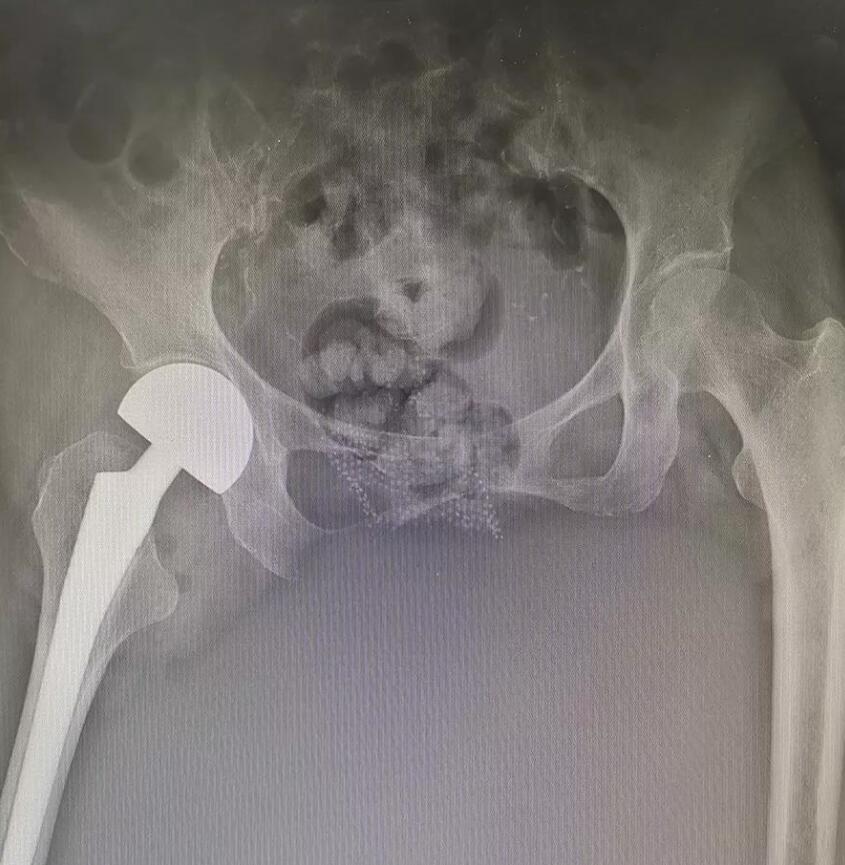

7月4日,我院接收了一名右髖部摔傷患者,此患者進(jìn)院時(shí)活動(dòng)受限,臥床難起,再加上此患者平素身體素質(zhì)很差,患有糖尿病20余年、患有冠心病8年、患腦梗塞7年、患高血壓5年,多種并發(fā)癥纏繞,進(jìn)院時(shí)神志淡漠,精神比較差。在經(jīng)過(guò)檢查和了解患者情況之后,擬以“右側(cè)股骨頸骨折”收住入院。

醫(yī)生在詳細(xì)了解了病人情況之后與醫(yī)院專(zhuān)家及醫(yī)護(hù)人員對(duì)病情進(jìn)行了深入研究,及時(shí)為患者制定了合理有效的治療方案。在與家屬溝通確定之后對(duì)患者進(jìn)行了半髖置換手術(shù),由于此患者的病情復(fù)雜,此手術(shù)風(fēng)險(xiǎn)比較大,手術(shù)難度也比較高。

然而就是在這種高難度、高復(fù)雜、高危險(xiǎn)的情況下,我院醫(yī)生依然順利地完成了半髖置換手術(shù)